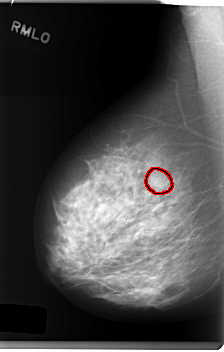

FILE: C_0243_1.RIGHT_MLO.OVERLAY

TOTAL_ABNORMALITIES 1

ABNORMALITY 1

LESION_TYPE MASS SHAPE OVAL MARGINS MICROLOBULATED

ASSESSMENT 4

SUBTLETY 2

PATHOLOGY BENIGN

TOTAL_OUTLINES 1

BOUNDARY